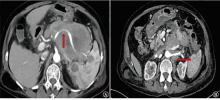

原发性胰腺淋巴瘤(PPL)是临床上较为罕见的胰腺肿瘤,其临床表现和实验室检查无明显特异性,影像学表现极易与胰腺导管腺癌等其他胰腺恶性肿瘤混淆。最终诊断可依靠超声或CT引导下穿刺取组织病理检查明确,避免不必要的剖腹探查手术。现报道1例接受2次胰腺组织活检得以确诊,应用miniCHOP、R-miniCHOP、R-CEOP、R+来那度胺方案治疗效果不佳的PPL病例,并文献复习,以期为该类患者的诊治提供帮助。